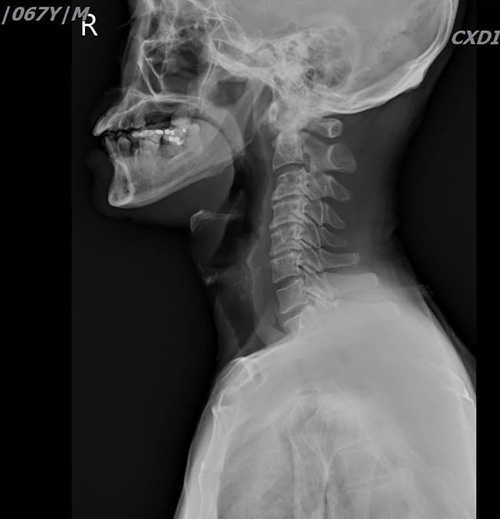

จากนั้นจึงเรียกภรรยาและลูก ๆ มาช่วยกัน จนภรรยาของตนถามว่า ฟันปลอมหายไปไหน จึงทำให้รู้ทันทีว่าสิ่งแปลกปลอมที่หลุดไปติดลำคอก็คือฟันปลอม ด้วยความตกใจจึงรีบขับรถด้วยตนเองไปยังโรงพยาบาลที่อยู่ใกล้เคียงเพื่อให้แพทย์ช่วยเหลือเอาฟันปลอมที่หลุดติดคอออกโดยเร็ว หลังจากแพทย์มีการเอกซเรย์และทำซีทีสแกนอย่างละเอียด แล้วก็พบว่ามีฟันปลอมหลุดไปติดที่หลอดอาหาร โชคดีที่ไม่หลุดไปติดที่หลอดลม จึงมีการระดมแพทย์ทั้งศัลยกรรมและแพทย์หู คอ จมูก จำนวน 5 คน มาช่วยกันทำการส่องกล้องดึงเอาฟันปลอมออกจากคอได้อย่างปลอดภัย จึงอยากฝากเตือนไปยังผู้ใช้ฟันปลอมทุกคนว่าควรมีการตรวจสอบตลอด ถ้าหากมีอาการหลวมก็ขอให้ไปพบทันตแพทย์ทำใหม่ อย่าประมาท

หมอจึงส่งเอกซเรย์คอมพิวเตอร์ จึงพบว่ามีฟันเทียมติดค้างในลำคอจริง